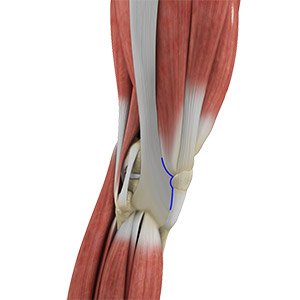

Knee Surgery

Knee surgery is a surgical procedure for the treatment of a knee injury or condition. The procedure involves repairing diseased or damaged structures of the knee joint in order to eliminate pain and restore normal function. The knee is a complex joint made up of different structures - bones, tendons, ligaments, and muscles.